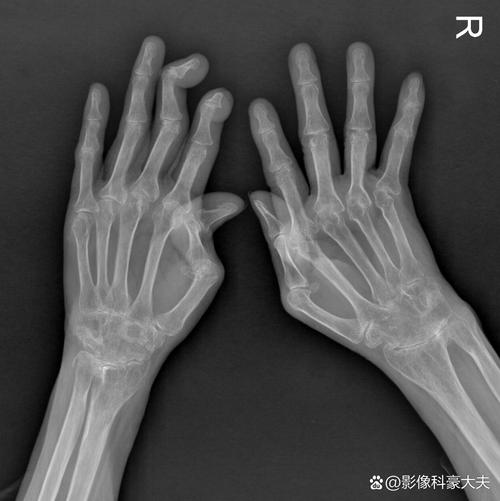

4. 骨侵蚀

核磁共振能检查类风湿

(图片来源网络,侵删)

• 虽然X光片也能发现骨侵蚀,但MRI能更早、更清晰地发现这些微小的骨质破坏,它不仅能看到骨皮质的缺损,还能评估侵蚀灶周围的炎症情况。